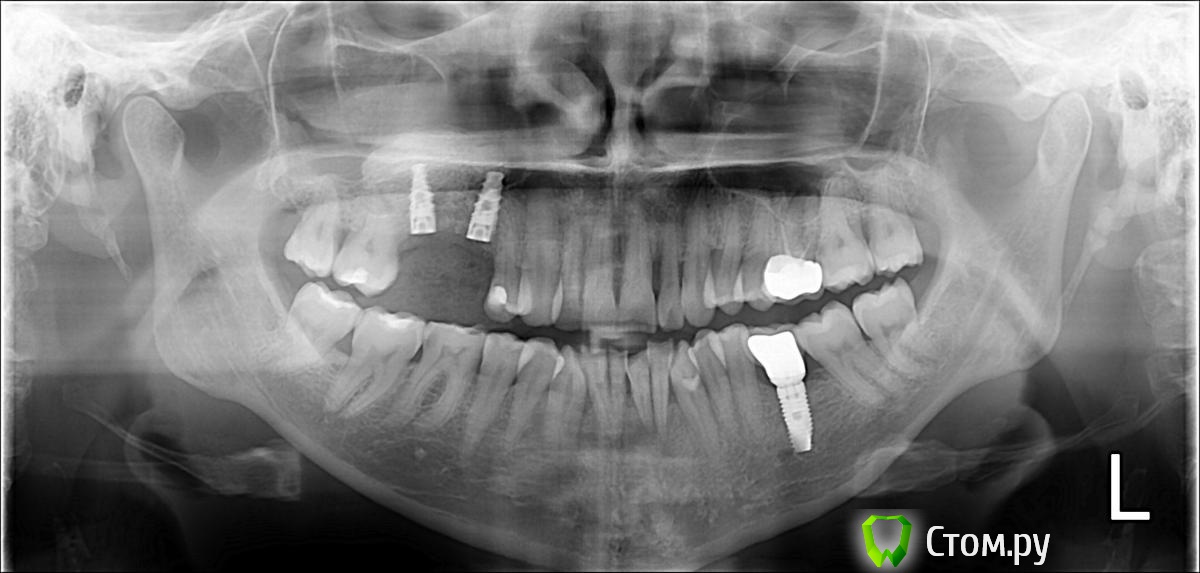

prioks Опубликовано 1 мая, 2014 Поделиться Опубликовано 1 мая, 2014 Здравствуйте! Подскажите, пожалуйста, есть ли на снимке признаки пародонтита. Нужно ли лечение, и если-да, то с чего начинать? Ссылка на комментарий

IvanK Опубликовано 1 мая, 2014 Поделиться Опубликовано 1 мая, 2014 Здравствуйте, да 1). проф гигиена + обучение гигиене,2). Консультация пародонтолога 1 Ссылка на комментарий

rivezico Опубликовано 2 мая, 2014 Поделиться Опубликовано 2 мая, 2014 +1 доктору, и это минимум, что вы можете и должны сделать. чем больше будете затягивать -тем выше вероятность самого печального исхода(потеря одного или больше зубов) и объективные данные любят изменяться , к сожалению, в геометрической прогрессии .. Ссылка на комментарий